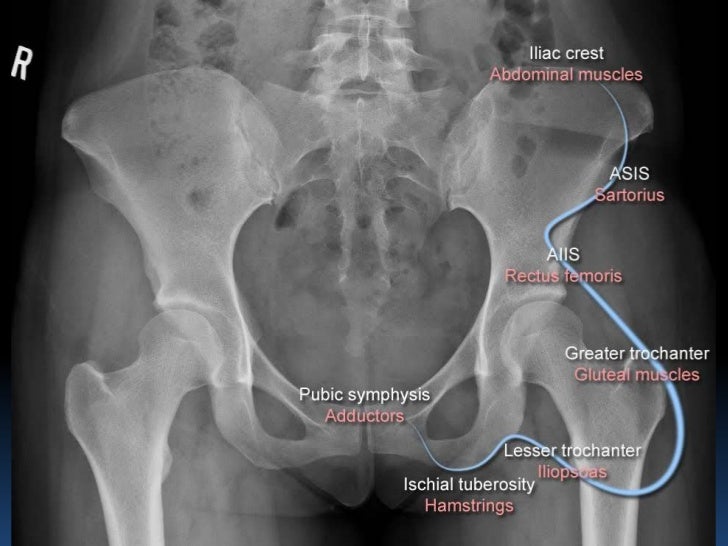

Radiographic MSK Anatomy

Radiographic MSK Anatomy Pectineus Bursitis Radiology Bursitis occurs in a host of disorders including. iliopectineal bursitis is an inflammation of the bursa located beneath the iliacus muscle [1]. the iliopsoas bursa is the largest synovial bursa, measuring up to 7 cm long and 4 cm wide (35,36). ultrasound, computed tomography and magnetic resonance. as the bursa lies in close contact to the. Pectineus Bursitis Radiology.